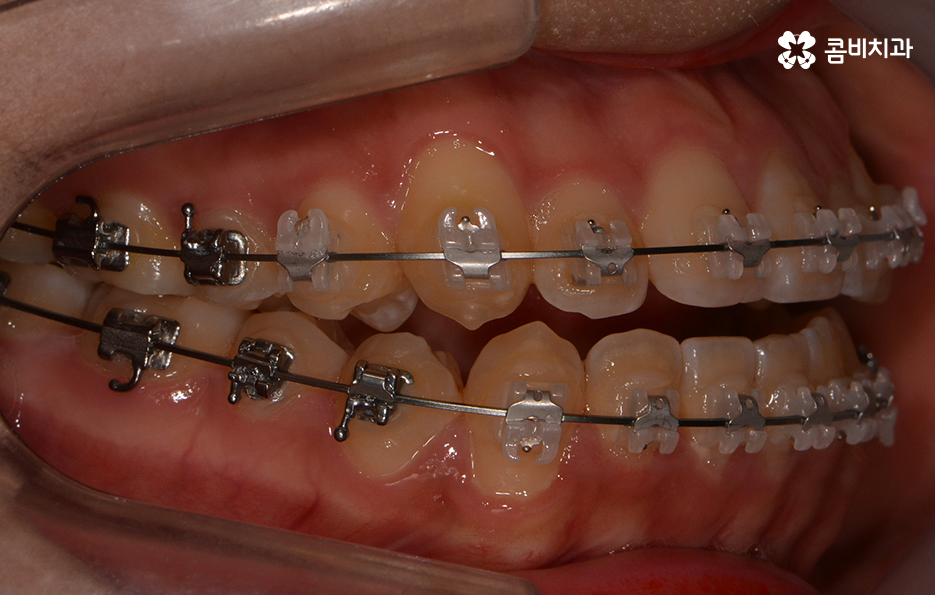

위 환자분의 경우에는 비발치로 송곳니 덧니 교정이

진행된 사례이며 전체 진료 기간은 약 1년 6개월가량이 소요되었습니다.

클리피씨 교정을 통해서 덧니가 개선되고 있는 경과

클리피씨 교정의 경우에는 일반적인 교정 방법에 비해서

진료 기간을 단축시킬 수 있다는 장점이 있는데

자가 결찰 장치로 서서히 치아를 지속적으로 이동시켜서

초기 통증은 줄이고 교정 기간의 단축이 가능합니다.

또한 교정 장치의 재질이 세라믹이기 때문에

심미적이라는 장점이 있으며 철사로 인한 찔림이